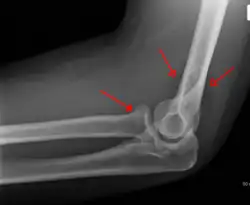

Une fracture de la tête radiale avec un signe de voile positif associé

La fracture peut se produire dans la capsule de l'articulation du coude. Elle n'est pas nécessairement visible directement sur une radio mais peut être détectée par le déplacement des coussinets adipeux à la suite de l'épanchement articulaire par le "signe du voile".

La lésion d'Essex-Lopresti est une fracture de la tête du radius concomitante avec une luxation de l'articulation radio-ulnaire distale et une lésion de la membrane interosseuse de l'avant-bras[2].